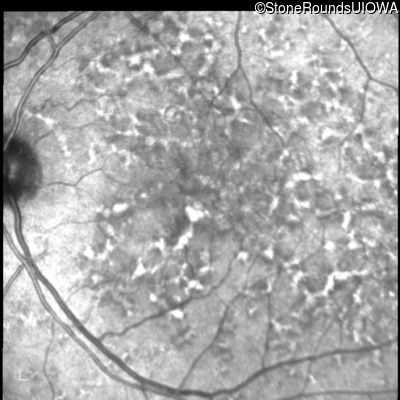

Blue Autofluorescence - Right - 20/20 -1 sc

Exemplar